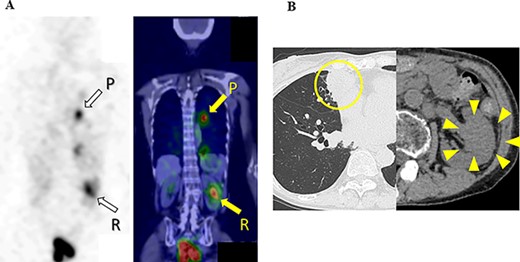

Ten months after the start of lenvatinib, CT showed a decrease in the sizes of pulmonary metastases (Fig. 3A) and renal metastasis (Fig. 3B) (tumor reduction rate: 45%). Remnant thyroid resection was performed and followed by RAI therapy with 100 mCi. In 131I scintigraphy, some lung metastases showed radioiodine uptake, whereas others did not. Radioiodine uptake was also observed in the left renal tumor, but not in the right kidney (Fig. 4A); therefore, the left renal tumor was finally confirmed as renal metastasis of PTC. Since the sizes of pulmonary and renal metastases both increased after the RAI therapy (tumor growth rate: 71%) (Fig. 4B), the administration of lenvatinib was resumed from a dose of 4 mg/day. After resuming lenvatinib, she has been in SD status for 6 months.

CT images of the chest and abdomen 10 months after the start of the administration of lenvatinib, and (A) pulmonary metastases decreased in size; (B) the size of the renal tumor decreased and the tumor plug disappeared.